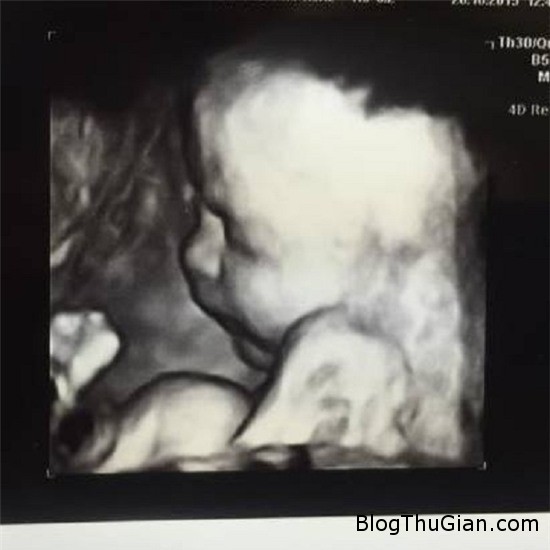

Hình ảnh thai nhi lúc còn ở trong bụng bà.